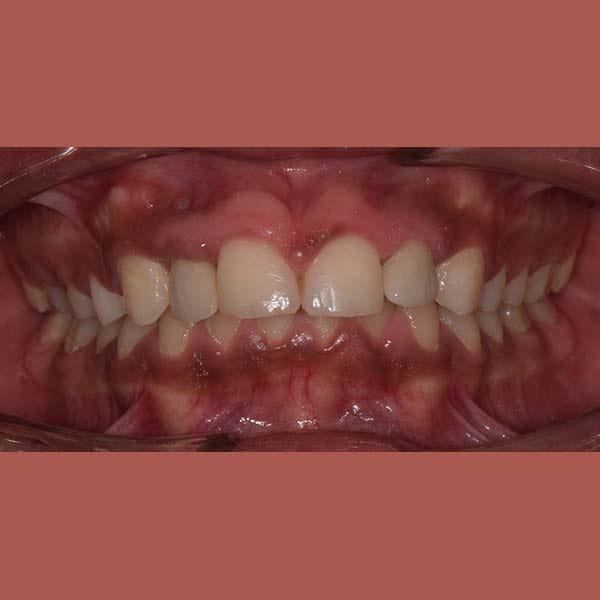

AFTER

عانت هذه السيدة من وجود عضة عميقة أمامية و غياب خلقي لسنين أماميين سفليين ،بالإضافة لتراكب و عدم ارتصاف الأسنان الأمامية العلوية بشكل جيد – تم فتح مسافة كافية لوضع غرستين سنيتين و تم تصخيح العضة العميقة تقويمياً